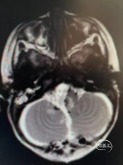

术前头部MRI

右侧桥小脑角区可见一不规则等T1、等-T2信号灶,大小约46*51*55mm3边界欠清,病灶突入四脑室内,第四脑室受压变窄,强化明显。